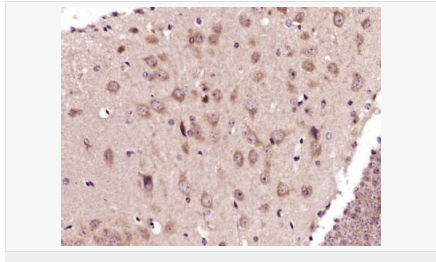

| 產品應用 | WB=1:500-2000 IHC-P=1:100-500 IHC-F=1:100-500 Flow-Cyt=3ug/test ICC=1:100-500 IF=1:100-500 (石蠟切片需做抗原修復) not yet tested in other applications. optimal dilutions/concentrations should be determined by the end user. |

| 免 疫 原 | KLH conjugated synthetic peptide derived from human ADORA2B:101-200/332 <Extracellular> |